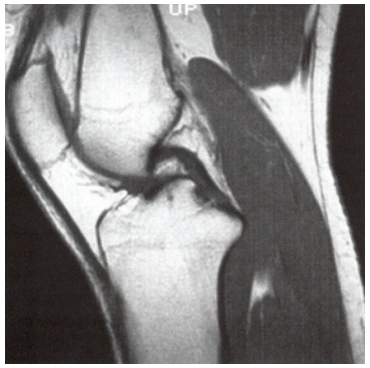

Nesta imagem de ressonância a seguir, observamos:

Fonte: https://doi.org/10.5114/pjr.2020.99415